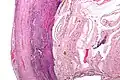

Pathology diagnosis of appendicitis can be made by detecting a neutrophilic infiltrate of the muscularis propria.

-

Micrograph of appendicitis and periappendicitis. H&E stain. -

Micrograph of appendicitis showing neutrophils in the muscularis propria. H&E stain. -

Acute suppurative appendicitis with perforation (at right). H&E stain.